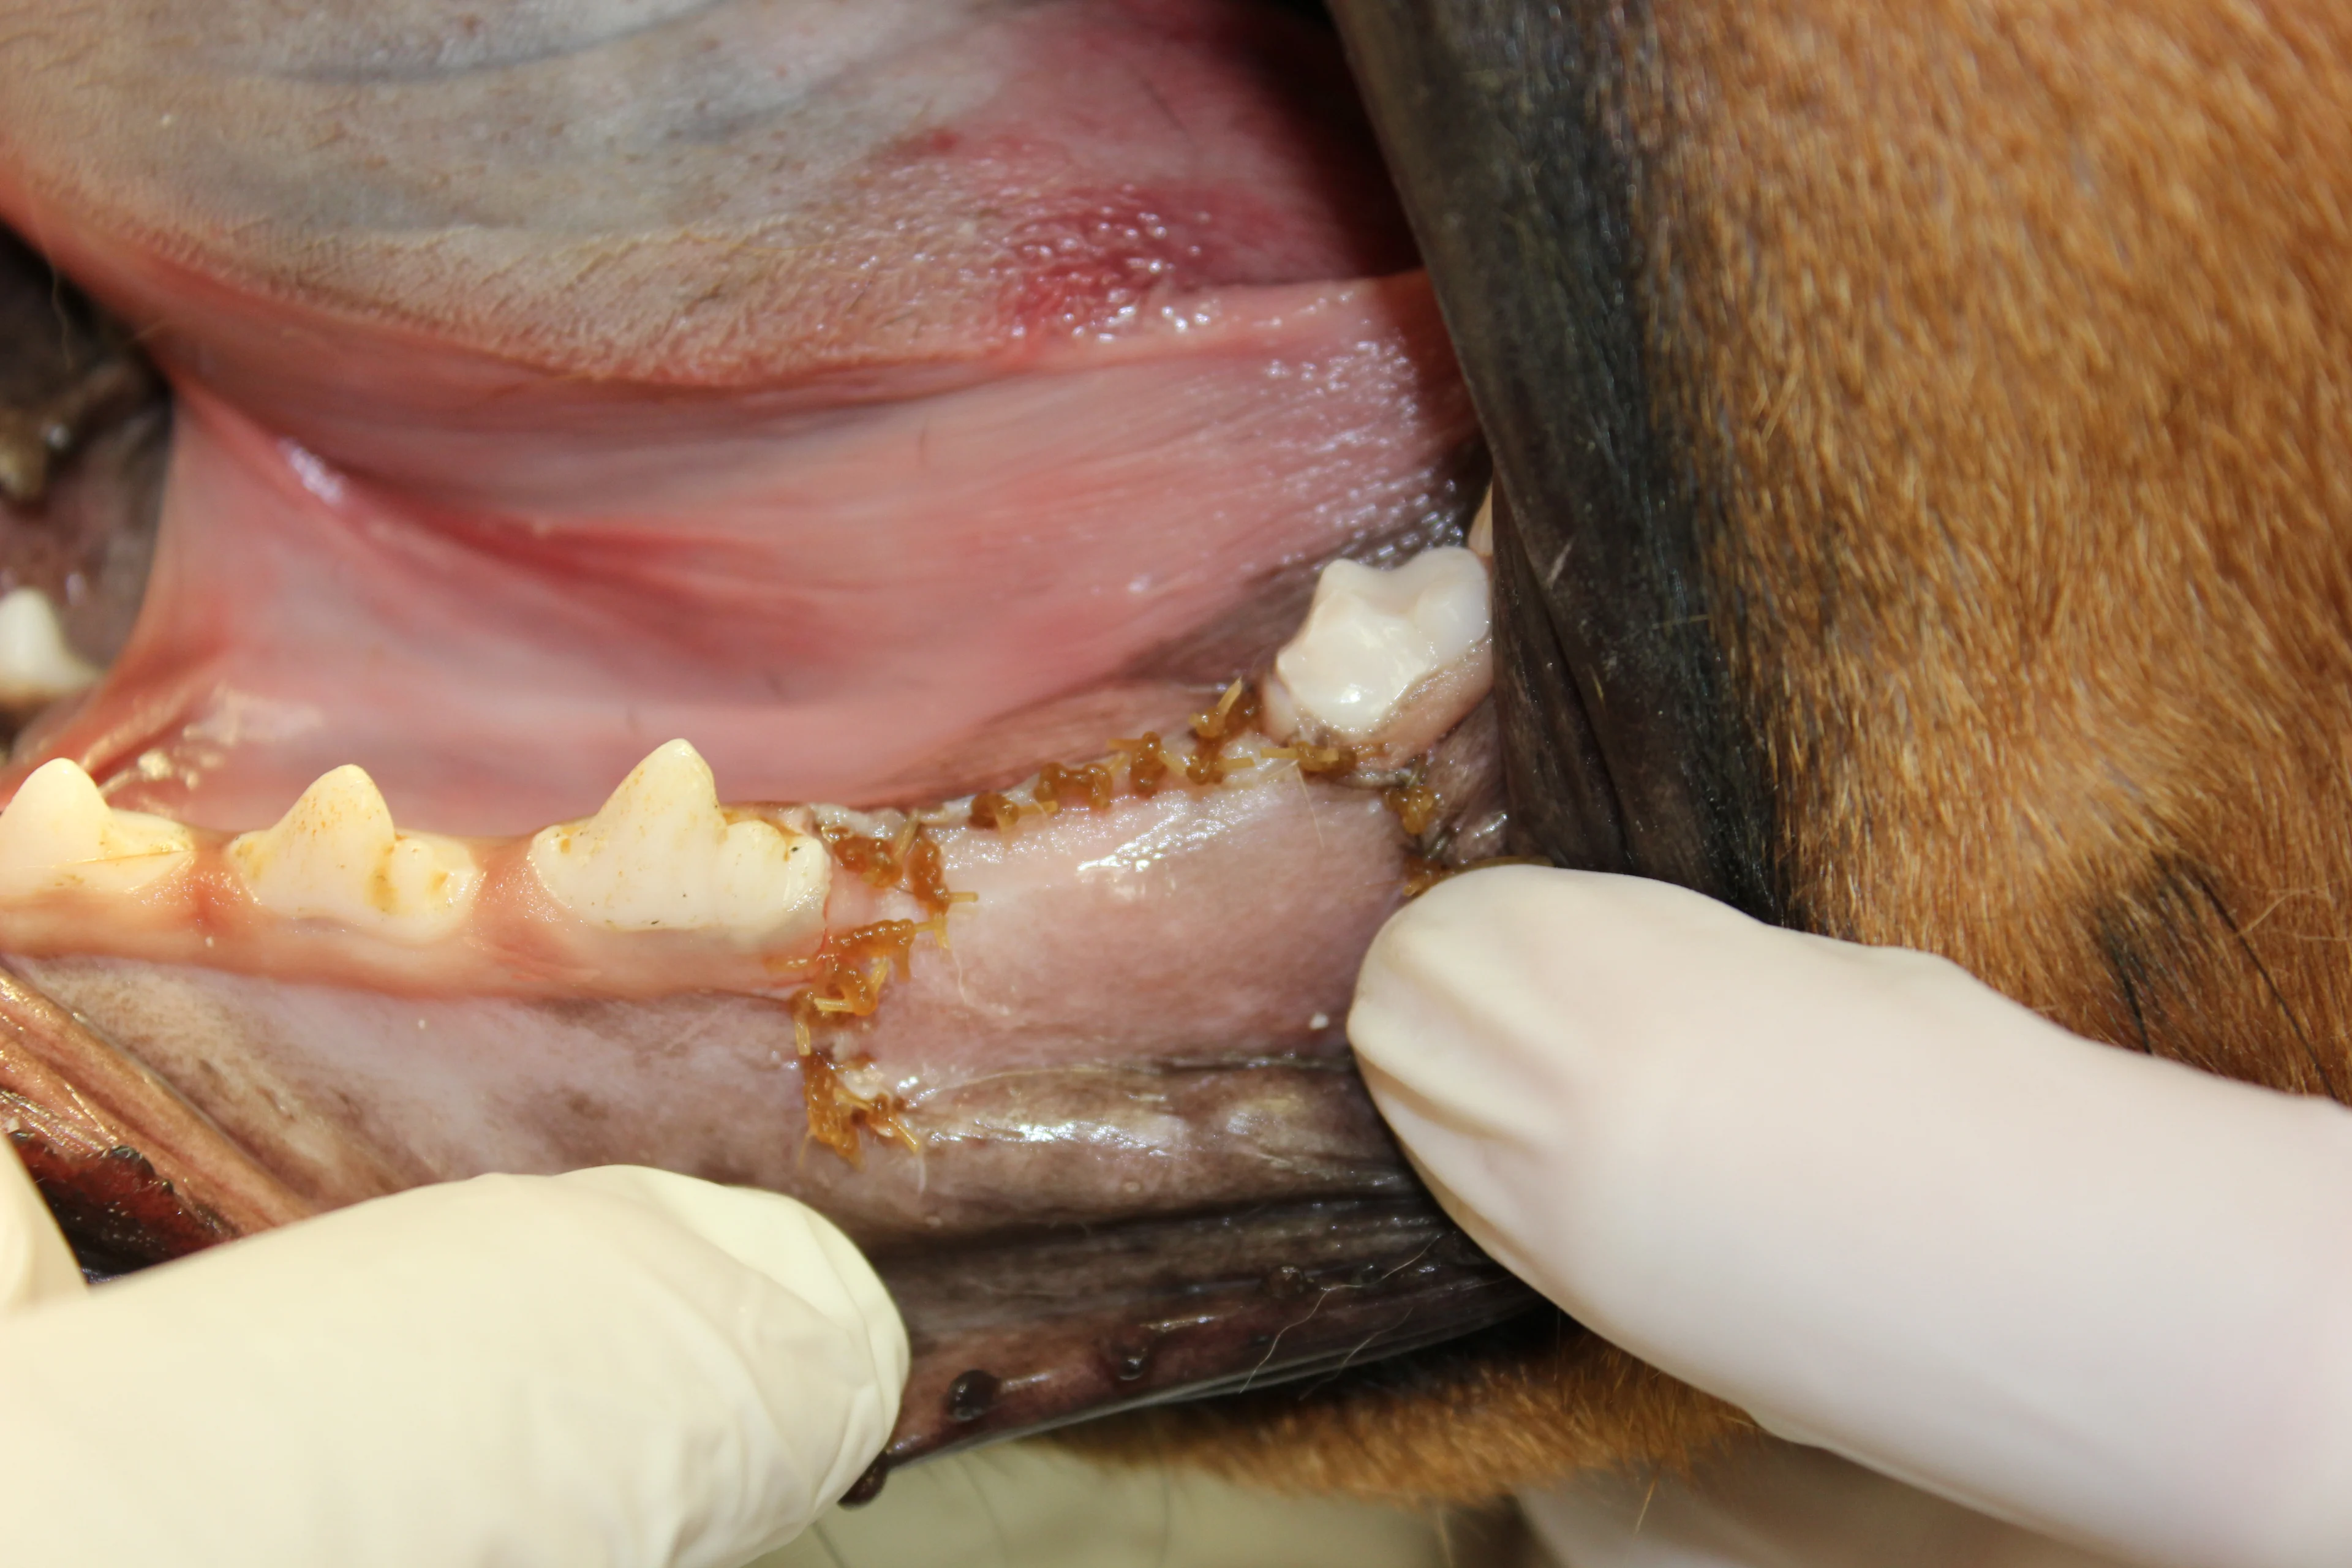

Step 10

Slightly free the alveolar mucosa from the lingual surface of the extraction site with the periosteal elevator. Place the periosteal elevator between the mucosa and alveolar bone while using a #8 round bur in a water-cooled high-speed handpiece to smooth the sharp edges from the alveolar bone (alveoloplasty). Palpate to ensure no sharp edges remain.